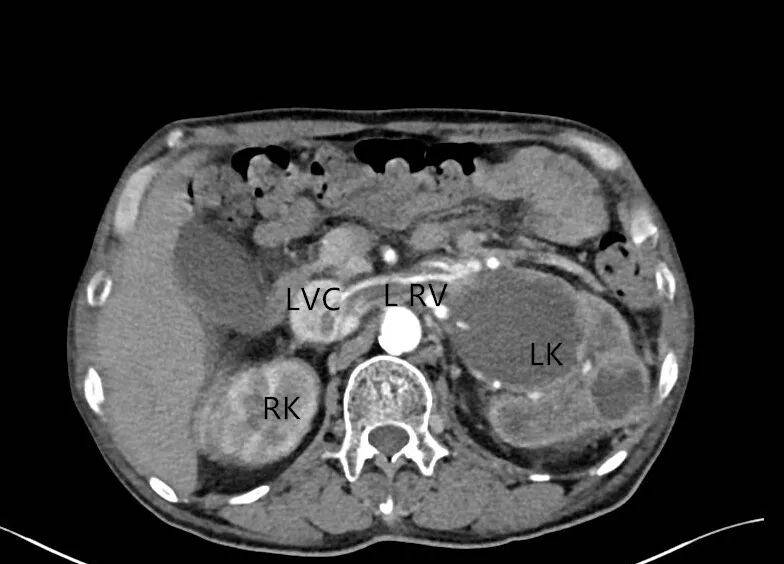

1. 左肾形态失常,体积增大,内部结构紊乱,呈混合性回声,以实性为主,内部可见不规则无回声。CDFI:混合性回声内部及周边未见明显血流信号(图 1、2)。

图 1 灰阶超声示肾癌超声表现( LK 左肾)